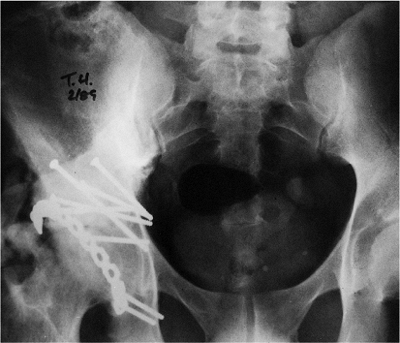

(c) associated both-column fractures, with a posterior wall or a

comminuted posterior-column lateral-dome involvement (Fig. 43.3)

Figure 43.3. An 18-year-old woman with a both-column right acetabular fracture. A. AP pelvis. B. Iliac oblique view. C. Obturator oblique view.

Figure 43.18. AP pelvis of patient in Figure 43.3,

at 5 months after extended iliofemoral approach. Significant (Brooker grade III) HO is present in the soft tissues of the right hip. |